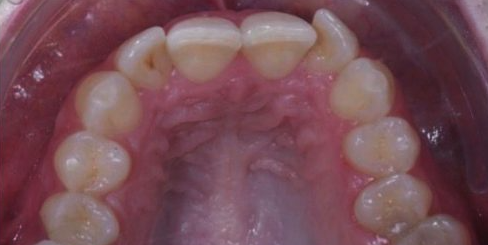

Upper incisor

Orthodontic treatment done on upper front teeth and also expanded the arch into a uniform curve.